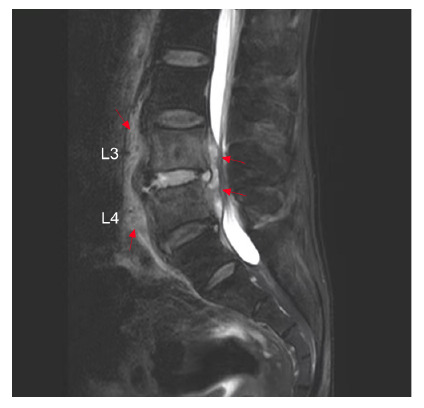

The appearances of a parrot's peak and petal rims in brucellar spondylitis.